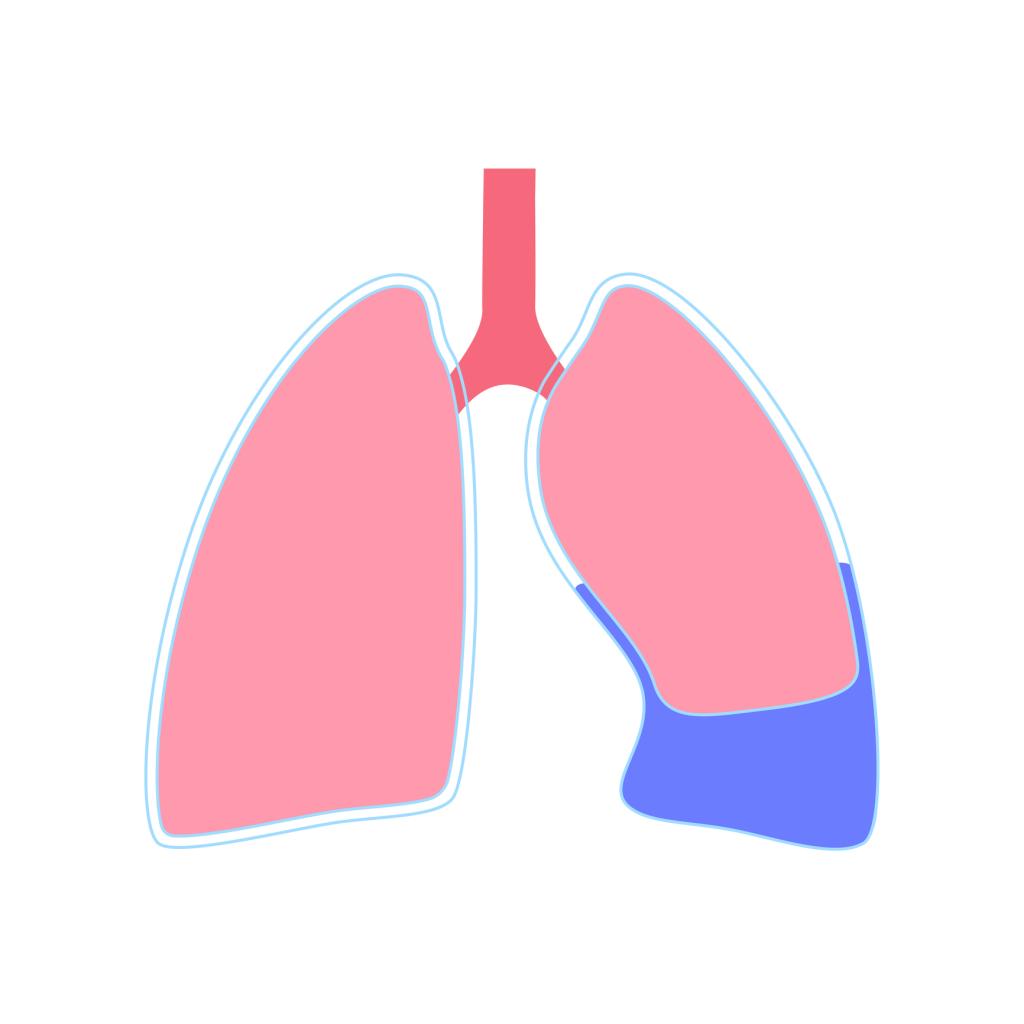

Je komt als ‘first responder’ bij een 28-jarige mountainbikester die gecrasht is en klinisch meerdere ribben heeft gebroken. In specifieke situaties met ernstig thoraxtrauma kan een naaldthoracocentese een levensreddende handeling zijn. In een recente cursus heb je de juiste uitvoering nog geoefend. Toen heb je ook gehoord dat thoracocenteses vaak onjuist worden uitgevoerd en bij de verkeerde indicaties, wat de nodige risico’s met zich meebrengt.